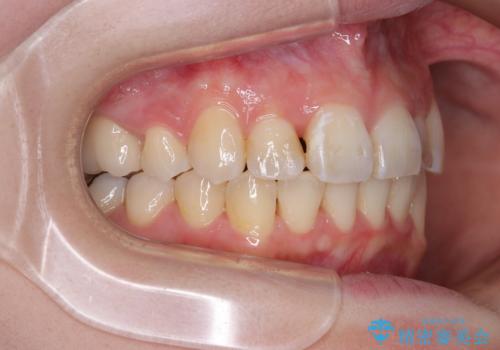

- 前歯のデコボコを気にして来院された患者様です。

上下の前歯にデコボコがあり、更にはディープバイトにより下顎前歯の大半が隠れている状態でした。

上顎左右第一小臼歯の2本を抜歯し、ワイヤー装置を使用して咬み合わせ高さを改善しながら、歯列を整えて行くこととしました。

事前にむし歯の疑いがある歯があり、処置を行いましたが、矯正治療中に失活してしまい、ワイヤー装置除去後に、根管治療とセラミッククラウンによる補綴治療を行いました。

矯正治療は2年半ほで無事におけることができました。